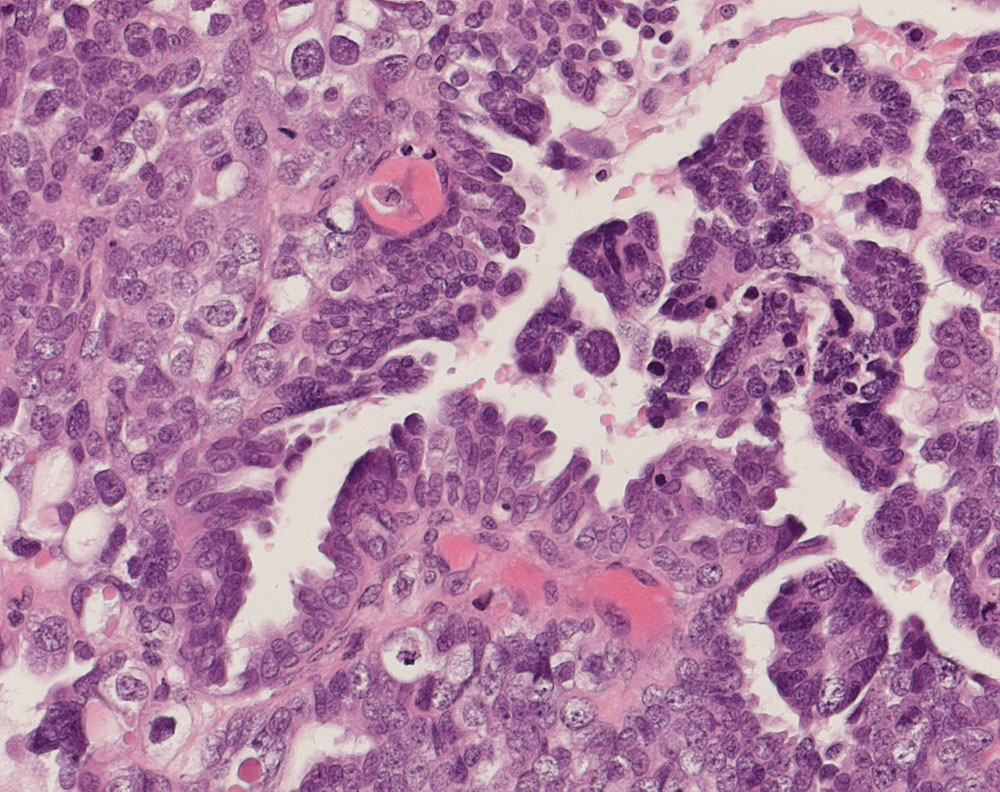

PathoPic ID 10933 - seröses Ovarialkarzinom high grade

seröses Ovarialkarzinom high grade

Teils solider, teils papillärer Tumor bestehend aus stark atypischen pleomorphen Tumorzellen mit starken Kerngrössenschwankungen. Mehrere Apoptosen.

Verdacht auf Ovarialkarzinom (CA125 > 2000u/l). CT: Vergrösserte Ovarian beidseits. Maligner Pleuraerguss Adenokarzinom.

Histologie

200